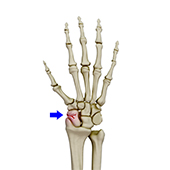

Scaphoid Fracture

Scaphoid fracture occurs due to a fall on an outstretched hand with complete weight falling on the palm. This fracture usually occurs during motor accidents or sports activities.